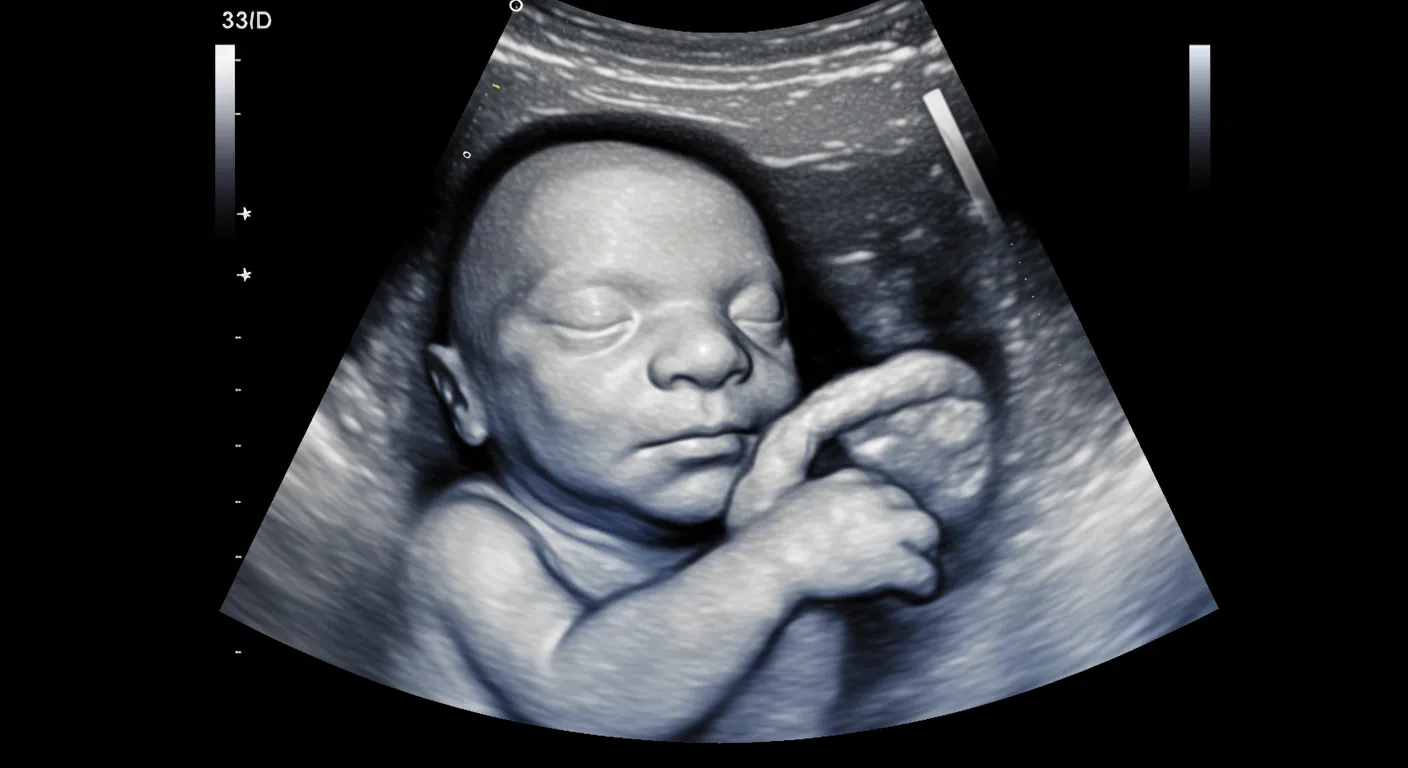

3D / 4D Ultrasound Scan

Experience advanced 3D and 4D ultrasound imaging, offering detailed views of your baby’s development to enhance bonding and informed decision-making.

At Klinik Pakar Wanita Aymira, we offer advanced 3D and 4D ultrasound imaging services to provide expectant parents with a detailed view of their developing baby. 3D ultrasound captures images from multiple angles, creating lifelike, three-dimensional images of your baby. 4D ultrasound adds the dimension of time, allowing you to see your baby’s movements in real-time, such as yawning, sucking, or stretching.

• Enhanced Visualization: Obtain clearer images of your baby’s facial features and movements, aiding in the early detection of certain abnormalities.